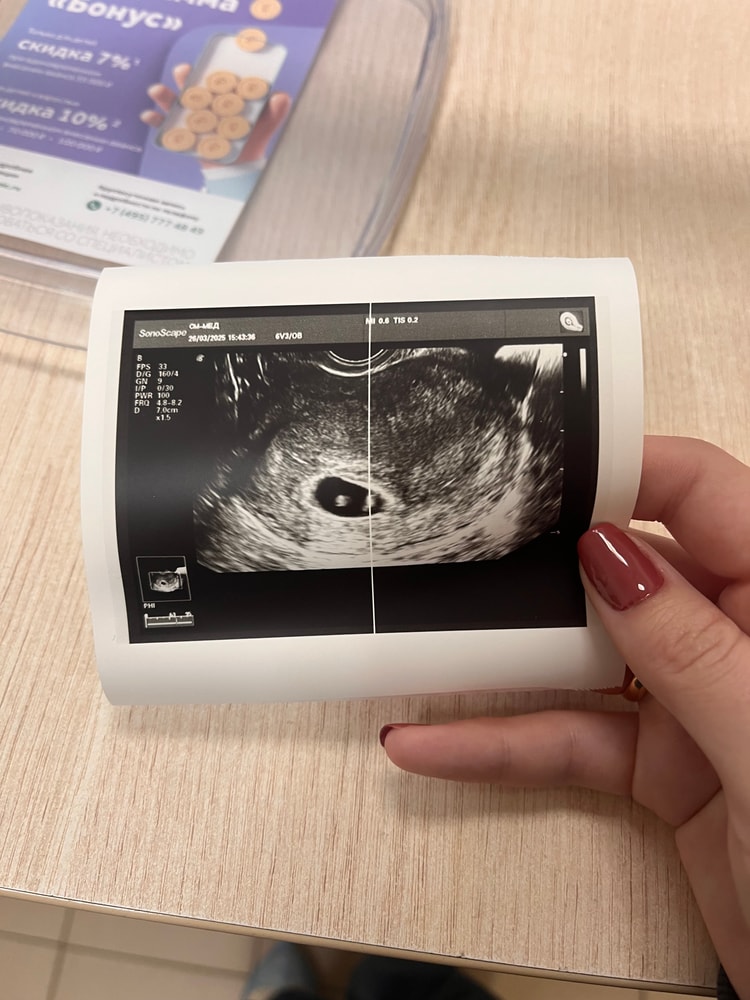

Елена, здравствуйте. Пя- 26,4 мм; ктр-7,4 мм

Сердцебиение Первое УЗИ, 5 недель